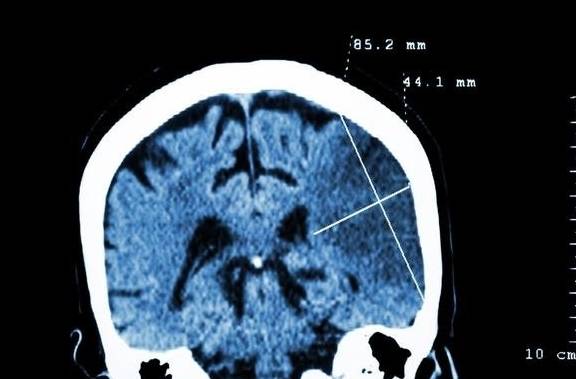

崔神医拿着手机安抚了对方半天 , 放下手机后面对华子询问的目光 , 他解释说 , 他外地的同学父亲前天因为高血压头晕 , 去医院查了个脑CT , 结果确诊为腔隙性脑梗死 。 听到得了“脑梗死”同学全家都担心得不行 , 但当地医生说是“腔隙性的脑梗死”不用紧张 , 没什么大事 。 可他同学还是不放心 , 所以打个电话问问他 , 这“腔隙性脑梗死”到底是个什么病?

崔神医说 , 腔隙性脑梗死是一种发病率随着年龄增大而增加的老年人常见病 。 他同学父亲患有高血压 , 而高血压又是腔隙性脑梗的高危因素 。 这种病老年人发病率高 , 但风险性较低 , 大多数患者没有后遗症 。 是细小的脑动脉末稍分支血管堵塞而引起的脑组织梗死 , 但影响的范围很小 , 梗死的脑组织被吞噬细胞清除后会留下空腔 , 所以称为腔隙性脑梗死 。

大多数人的腔隙性脑梗死不影响大脑功能区 , 几乎没有任何症状 。 很多患者都是在查CT或是核磁的时候才发现自己有腔隙性脑梗死 。 部分患者梗死发生在功能区时 , 可能会伴有短暂的意识、语言障碍 , 或是短暂的头晕、站立不稳、晕厥等症状 。 但腔隙性脑梗死影响的范围很小 , 造成的功能障碍很快就会被正常的脑组织代偿 , 并不会有很重的后遗症 。